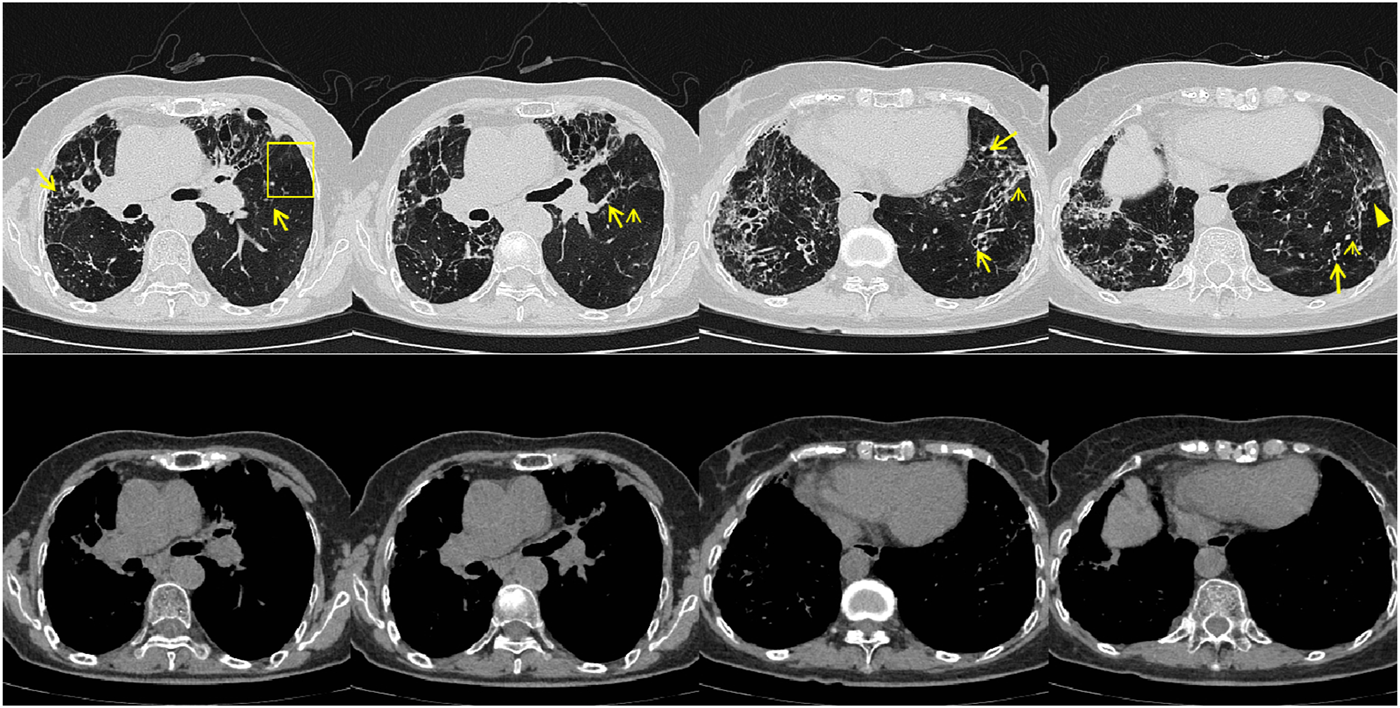

From June to September 2024, the patient followed up at the outpatient clinic. Chest CT showed that the lesions in both lungs were partially absorbed (Figures 5, 6), inflammatory markers returned to normal (Table 1), FeNO and peripheral blood eosinophils significantly decreased (Table 1, 3). By asthma symptom assessment, the patient’s cough severity score on the Cough Evaluation Test (CET) was 7, the Asthma Control Questionnaire (ACT) score was 25, and the Asthma Control Questionnaire-5 (ACQ-5) score was 0.8, indicating a significant improvement in pulmonary ventilation function (Table 2).

FIGURE 5

Patient’s chest CT imaging on Jun 17, 2024. The chest computed tomography showed remission of mucus plugging (narrow arrows), bronchopneumonia (arrow heads) and tree-in-bud opacities (yellow boxes) than previous images, indicating that the treatment was effective.